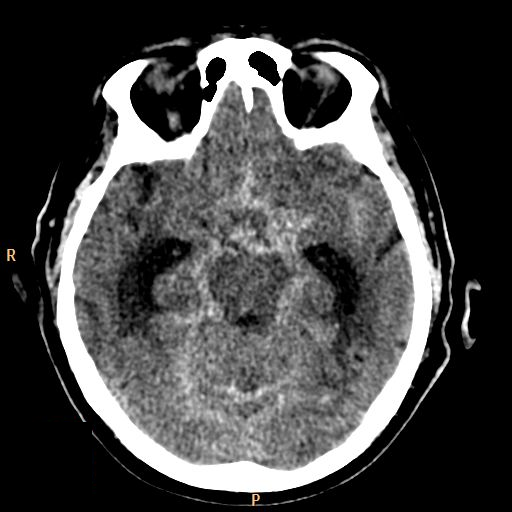

The key question whether the patient ha intracranial hematoma, which causes mass effect and later leads to vasoconstriction. In the presence of open skull fracture signed by liquorrhea severe infection and herniation might occur. To exclude intracranial hemorrhage CT is the modality of choice.

All three types of intracranial hematoma can occur as a result of head trauma:

• Subarachnoid hemorrhage develops after vascular injury or aneurysm rupture.

6. Middle aged female fell of a ladder. On the unenhanced CT scan the basal cisterns are filled corresponding to a subarachnoid hemorrhage.